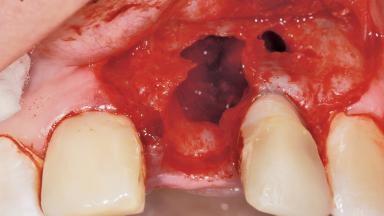

A 36-year-old female patient was referred for the replacement of the upper left central incisor (tooth 21), which had fractured. Although the tooth had been asymptomatic for many years, the crown began to loosen, at which time she presented to her dentist for an assessment. Teeth 21 and 22 had both been endodontically treated many years previously. She was a healthy individual and a non-smoker.

The crown of tooth 21 was splinted to the adjacent teeth with composite resin, and the gingiva was inflamed.

Bone Volume | Deficient horizontally, requiring prior grafting |